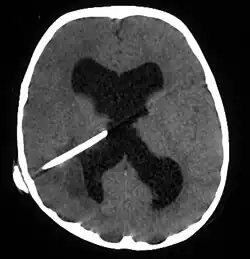

Brain abscess in a person with a CSF shunt. The abscess is the darker gray region in the lower left of the image (corresponding to the right parietal lobe). The lateral ventricles are visible in black in the center of the brain, adjacent to the abscess.[1]